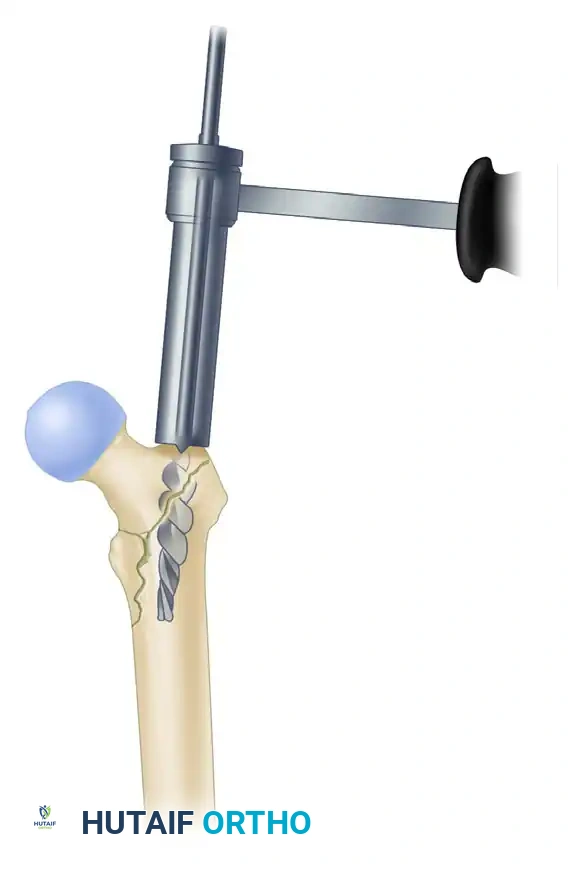

3. Proximal Reaming and Canal Preparation

- Once the guide pin is perfectly positioned, use the rigid proximal entry reamer to ream over the guide pin. Advance the reamer to a depth just below the level of the lesser trochanter.

- Ream the diaphyseal canal sequentially to a diameter 1.5 mm larger than the selected diameter of the intramedullary nail.

🚨 SURGICAL WARNING: The Anterior Bow

Pay careful attention to the anterior radius of curvature (bow) of the femur on the lateral fluoroscopic view. If the patient has a pronounced anterior bow, it may be necessary to over-ream by 2.0 mm larger than the nail diameter to prevent the distal tip of a straight nail from impinging on and perforating the anterior cortex.